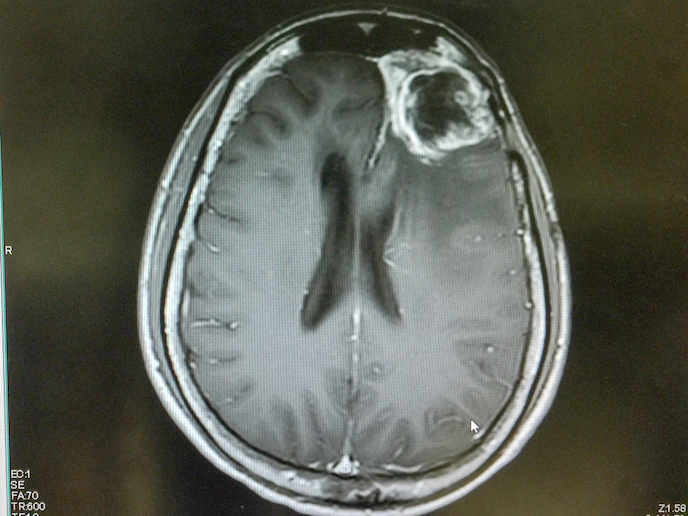

Glioblastoma is a rare and extremely aggressive type of brain cancer with a very high mortality rate. In fact, the average length of survival for most patients receiving treatment is a mere 15 months. But a promising new compound developed by Laminar Pharma(opens in new window) called LAM561(opens in new window) could help answer this unmet clinical need. LAM561 is a bioactive lipid that is inserted into the surface lipids of cancer cells, increasing the membrane fluidity and dislodging the key signalling proteins responsible for spreading the tumour. As a result, the lipid can enter the cell and regulate enzyme activity, altering the entire cell’s membrane composition and dissolving the cancer-associated lipid rafts. With the support of the EU-funded CLINGLIO(opens in new window) project, this novel therapy for treating patients with newly diagnosed glioblastoma is one step closer to possibly improving patients’ quality of life and life expectancy.